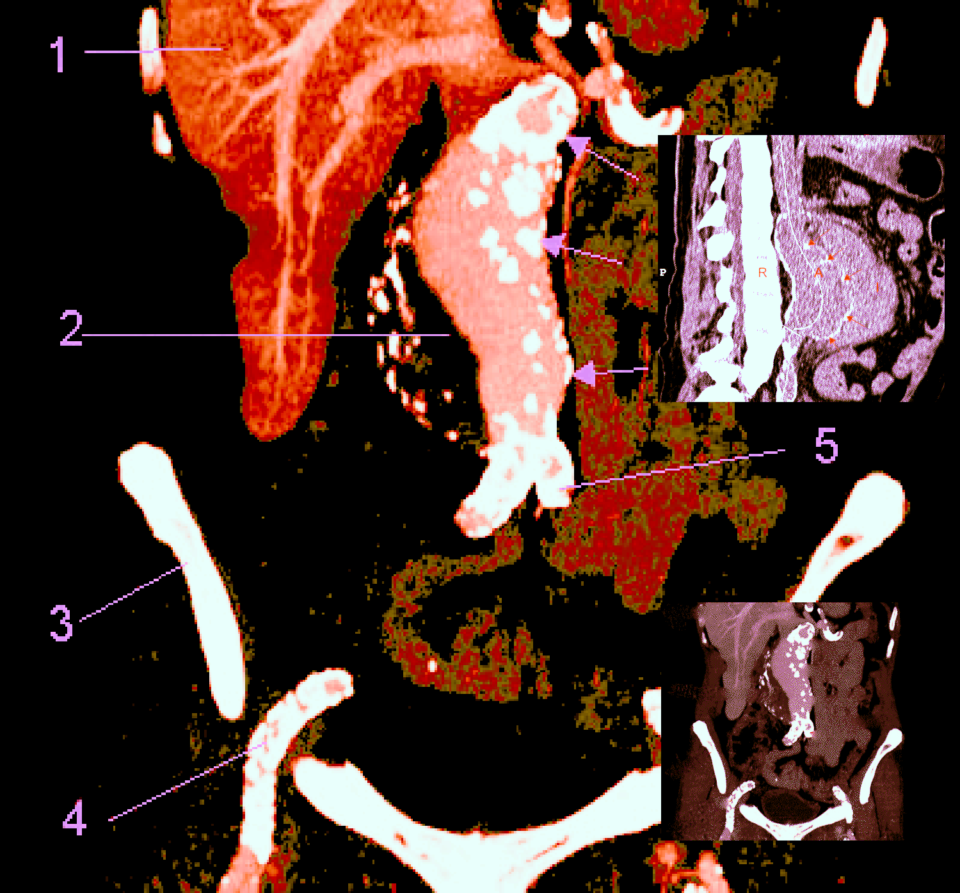

Les mesures effectuées sur un anévrisme doivent inclure le diamètre total incluant le thrombus (flèche bleue) et la lumière. Les images suivantes montrent un anévrisme majeur de 8cm partiellement thrombosé. Il est possible d’utiliser le doppler couleur dans ces circonstances, ce qui permettra d’objectiver l’absence de flux au niveau de la thrombose. L’examen sera complété par une coupe sagittale afin de préciser l’étendue de l’anévrisme (seconde image).

La grande majorité (85%) des anévrismes de l’aorte abdominale est située sous les artères rénales et les artères iliaques sont souvent aussi anévrismales. Si l’anévrisme englobe l’origine des artères rénales, on parle alors d’anévrisme pararénal.

L’angioscanner aorto-iliaque est plus invasif mais plus reproductible que l’échographie et moins opérateur dépendant. C’est l’examen de choix avant un traitement par endoprothèse ou par chirurgie classique. Il permet les mesures exactes (« sizing ») de l’anatomie de l’anévrysme, de l’aorte et des artères iliaques avant mise en place d’une endoprothèse. Il permet la recherche d’autres anévrysmes au niveau fémoro-poplités et d’étudier l’ensemble de l’aorte.